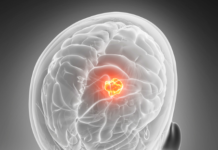

California’daki Stanford Üniversitesi’nden araştırmacılar, çocukluk döneminde Pokémon gibi video oyunlarına yoğun şekilde maruz kalmanın beynin belirli bölgelerini harekete geçirdiğini buldu.

Stanford Üniversitesi’ndeki psikologlar, çocukluk döneminde bu tekrarlanan görsel uyarıcıların, ekranın önünde geçirilen saat sayısı ile birlikte beynin belirli bölgelerini harekete geçirdiğini keşfetti.

Araştırmacılar, daha küçükken yoğun biçimde Pokémon oynayan 11 yetişkin aldı; Gomez de deneyde yer aldı. Katılımcıların tümüne MRI taraması yapıldı.

Araştırmacılar yüzlerce Pokémon karakteri gösterdiler. Beklenildiği gibi, Pokémon’u çocuk olarak oynayanların beyinleri görüntülere, oyunu çocuk olarak oynamayanlardan daha fazla tepki verdi.

Katılımcılar arasında tutarsız olan Pokémon için beyin aktivasyonları bölgesiydi: kulakların arkasında bulunan ve oksipitotemporal sulkus denilen bir alan. Görünüşe göre bu bölge normalde hayvanların görüntülerine cevap verebiliyor – ve Pokémon karakterleri hayvana benziyor.

Stanford Üniversitesi, Beşeri Bilimler ve Bilimler Fakültesi’nden Prof. Kalanit Grill-Spector, “Çalışmamızdan çıkarılan derslerden birinin bence”, “merkezi vizyonumuz tarafından harekete geçirilen bu beyin bölgelerinin özellikle geniş deneyime açıktır” dedi.

Beynin usta bir doğaçlamacı olduğunu ekliyor. Pokémon karakterlerine adanmış yeni aktivasyonlar oluşturabilir, ancak süreçte belirli kuralları izler. Biri, bu aktivasyonların nerede gerçekleştiğine işaret eder.